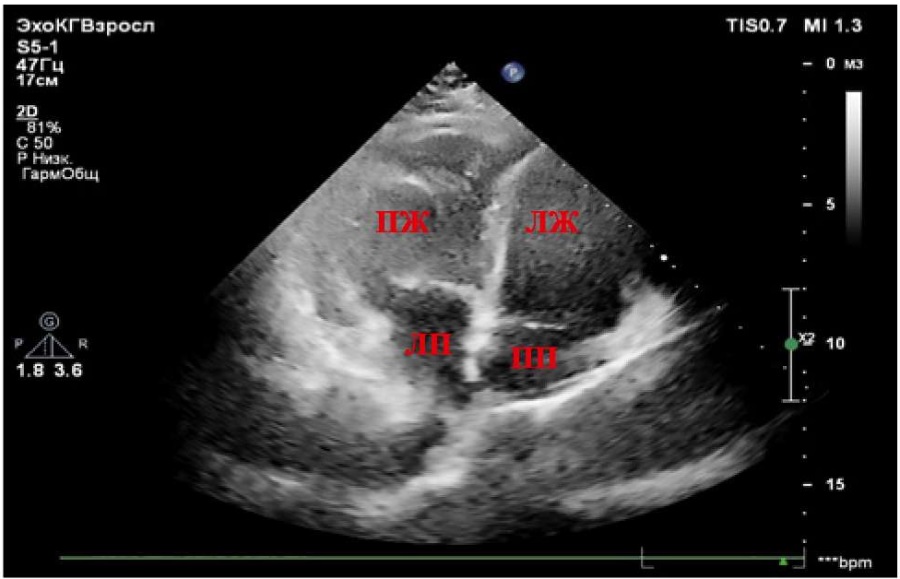

При проведении ЭхоКГ, представленной на рисунках 1–4, выявлено правосформированное леворасположенное сердце. Печень расположена в анатомически положенном месте (справа). Анатомически ПП (ориентир — заслонка полой вены) соединён с анатомически ЛЖ (анатомический ориентир — гладкая эндокардиальная поверхность), расположенным справа (дискордантное АВ-соединение). Диаметр ПП — 36×42 мм. Базальный диаметр ЛЖ из апикальной позиции (приточный отдел) — 38 мм, глобальная сократимость не снижена. Толщина боковой стенки ЛЖ — 7–8 мм. ПП соединяется с ЛЖ посредством двустворчатого (анатомически митрального) клапана, крепление створок которого расположено ниже крепления створок ТК. Митральная регургитация (+/++). От анатомически ЛЖ отходит ствол ЛА (несёт венозную кровь), с наличием митрально-легочного фиброзного продолжения. Диаметр ЛА на уровне клапана — 26 мм. Максимальный градиент на клапане ЛА — 8 мм рт. ст. Пульмональная регургитация (+). Визуализируются бифуркация и ветви ЛА, не расширены. Слева от ЛЖ располагается анатомически ПЖ (анатомический ориентир — модераторный пучок и трабекулярность). ПЖ соединяется с анатомически ЛП посредством анатомически ТК. Трикуспидальная регургитация (++/+++), створки утолщены. Сухожильные хорды ТК крепятся к перегородке и трабекулам ПЖ. Базальный диаметр ПЖ из апикальной позиции — 49 мм. Фракция изменения площади (ФИП) ПЖ — 40% (норма — более 35%) [7][8]. Систолическая экскурсия плоскости трикуспидального кольца в М-режиме (TAPSE) — 14,7 мм (норма — более 17 мм) [7][8]. Толщина боковой стенки ПЖ — 7–8 мм, МЖП — 9 мм. Диаметр ЛП — 46×68 мм. Объём ЛП — 80 мл. От анатомически ПЖ отходит Ао (несёт артериальную кровь). Диаметр корня Ао — 34 мм, восходящего отдела Ао — 29 мм, дуга Ао — 29 мм. Аортальный клапан (АК) двухстворчатый, регургитации нет. Максимальный градиент на АК — 8 мм рт. ст. Скорость кровотока в нисходящем отделе Ао в пределах нормы. Отсутствует контакт между артериальным (анатомически ТК) АВ-клапаном и магистральным сосудом (Ао), что свидетельствует об инверсионном положении сосудов. Ао расположена спереди и слева от ЛА. Патологические шунты через МПП и МЖП при цветовом картировании не регистрируются, смещения септальной створки ТК нет. Допплер: ЕТК — 108 см/сек., АТК — 32 см/сек., ебокТК — 19 см/сек., еМЖП — 11,7 см/сек., sТК — 8 см/сек. (норма для ТК — более 9,5 см/сек.) [7], что позволяет косвенно судить о наличии нарушения регионарной систолической функции ПЖ. ta-eТК — 625 мс, tsТК — 354 мс, Teim-индекс — 0,77 (норма — менее 0,54), что также косвенно указывает на наличие нарушения регионарной систолической функции ПЖ. Е/еТКср 7,5 — косвенный признак отсутствия высокого конечного диастолического давления в ПЖ [7][8].

Рисунок 1. Апикальная четырёхкамерная позиция (инверсия желудочков). Анатомический ориентир — ПП (заслонка полой вены), ЛЖ (гладкая эндокардиальная поверхность), ПЖ (модераторный пучок и трабекулярность).

Примечание: ПЖ — правый желудочек, ЛЖ — левый желудочек, ЛП — левое предсердие, ПП — правое предсердие.